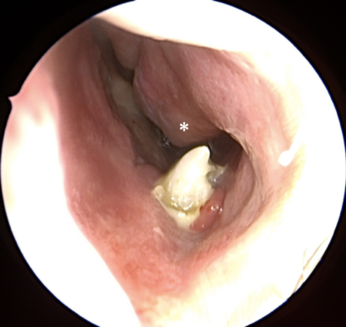

Sự hiện diện của răng thừa sẽ gây cản trở quá trình mọc và sắp xếp của các răng cửa hàm trên. Chúng có thể làm lệch hoặc ngăn cản sự mọc của các răng cửa giữa; gây mọc lệch vị trí, dịch chuyển hoặc xoay răng cửa hoặc răng cửa bị lệch về phía môi. Các biến chứng ít gặp hơn liên quan đến răng cửa vĩnh viễn bao gồm giãn chân răng đang phát triển, tiêu chân răng và chết tủy răng. Ngoài ra, các biến chứng liên quan đến răng thừa bao gồm mọc răng thừa vào khoang mũi, xoang hàm và phát triển nang răng đã được báo cáo.

Răng thừa gây nang xương hàm trên Răng thừa mọc vào tiền đình mũi